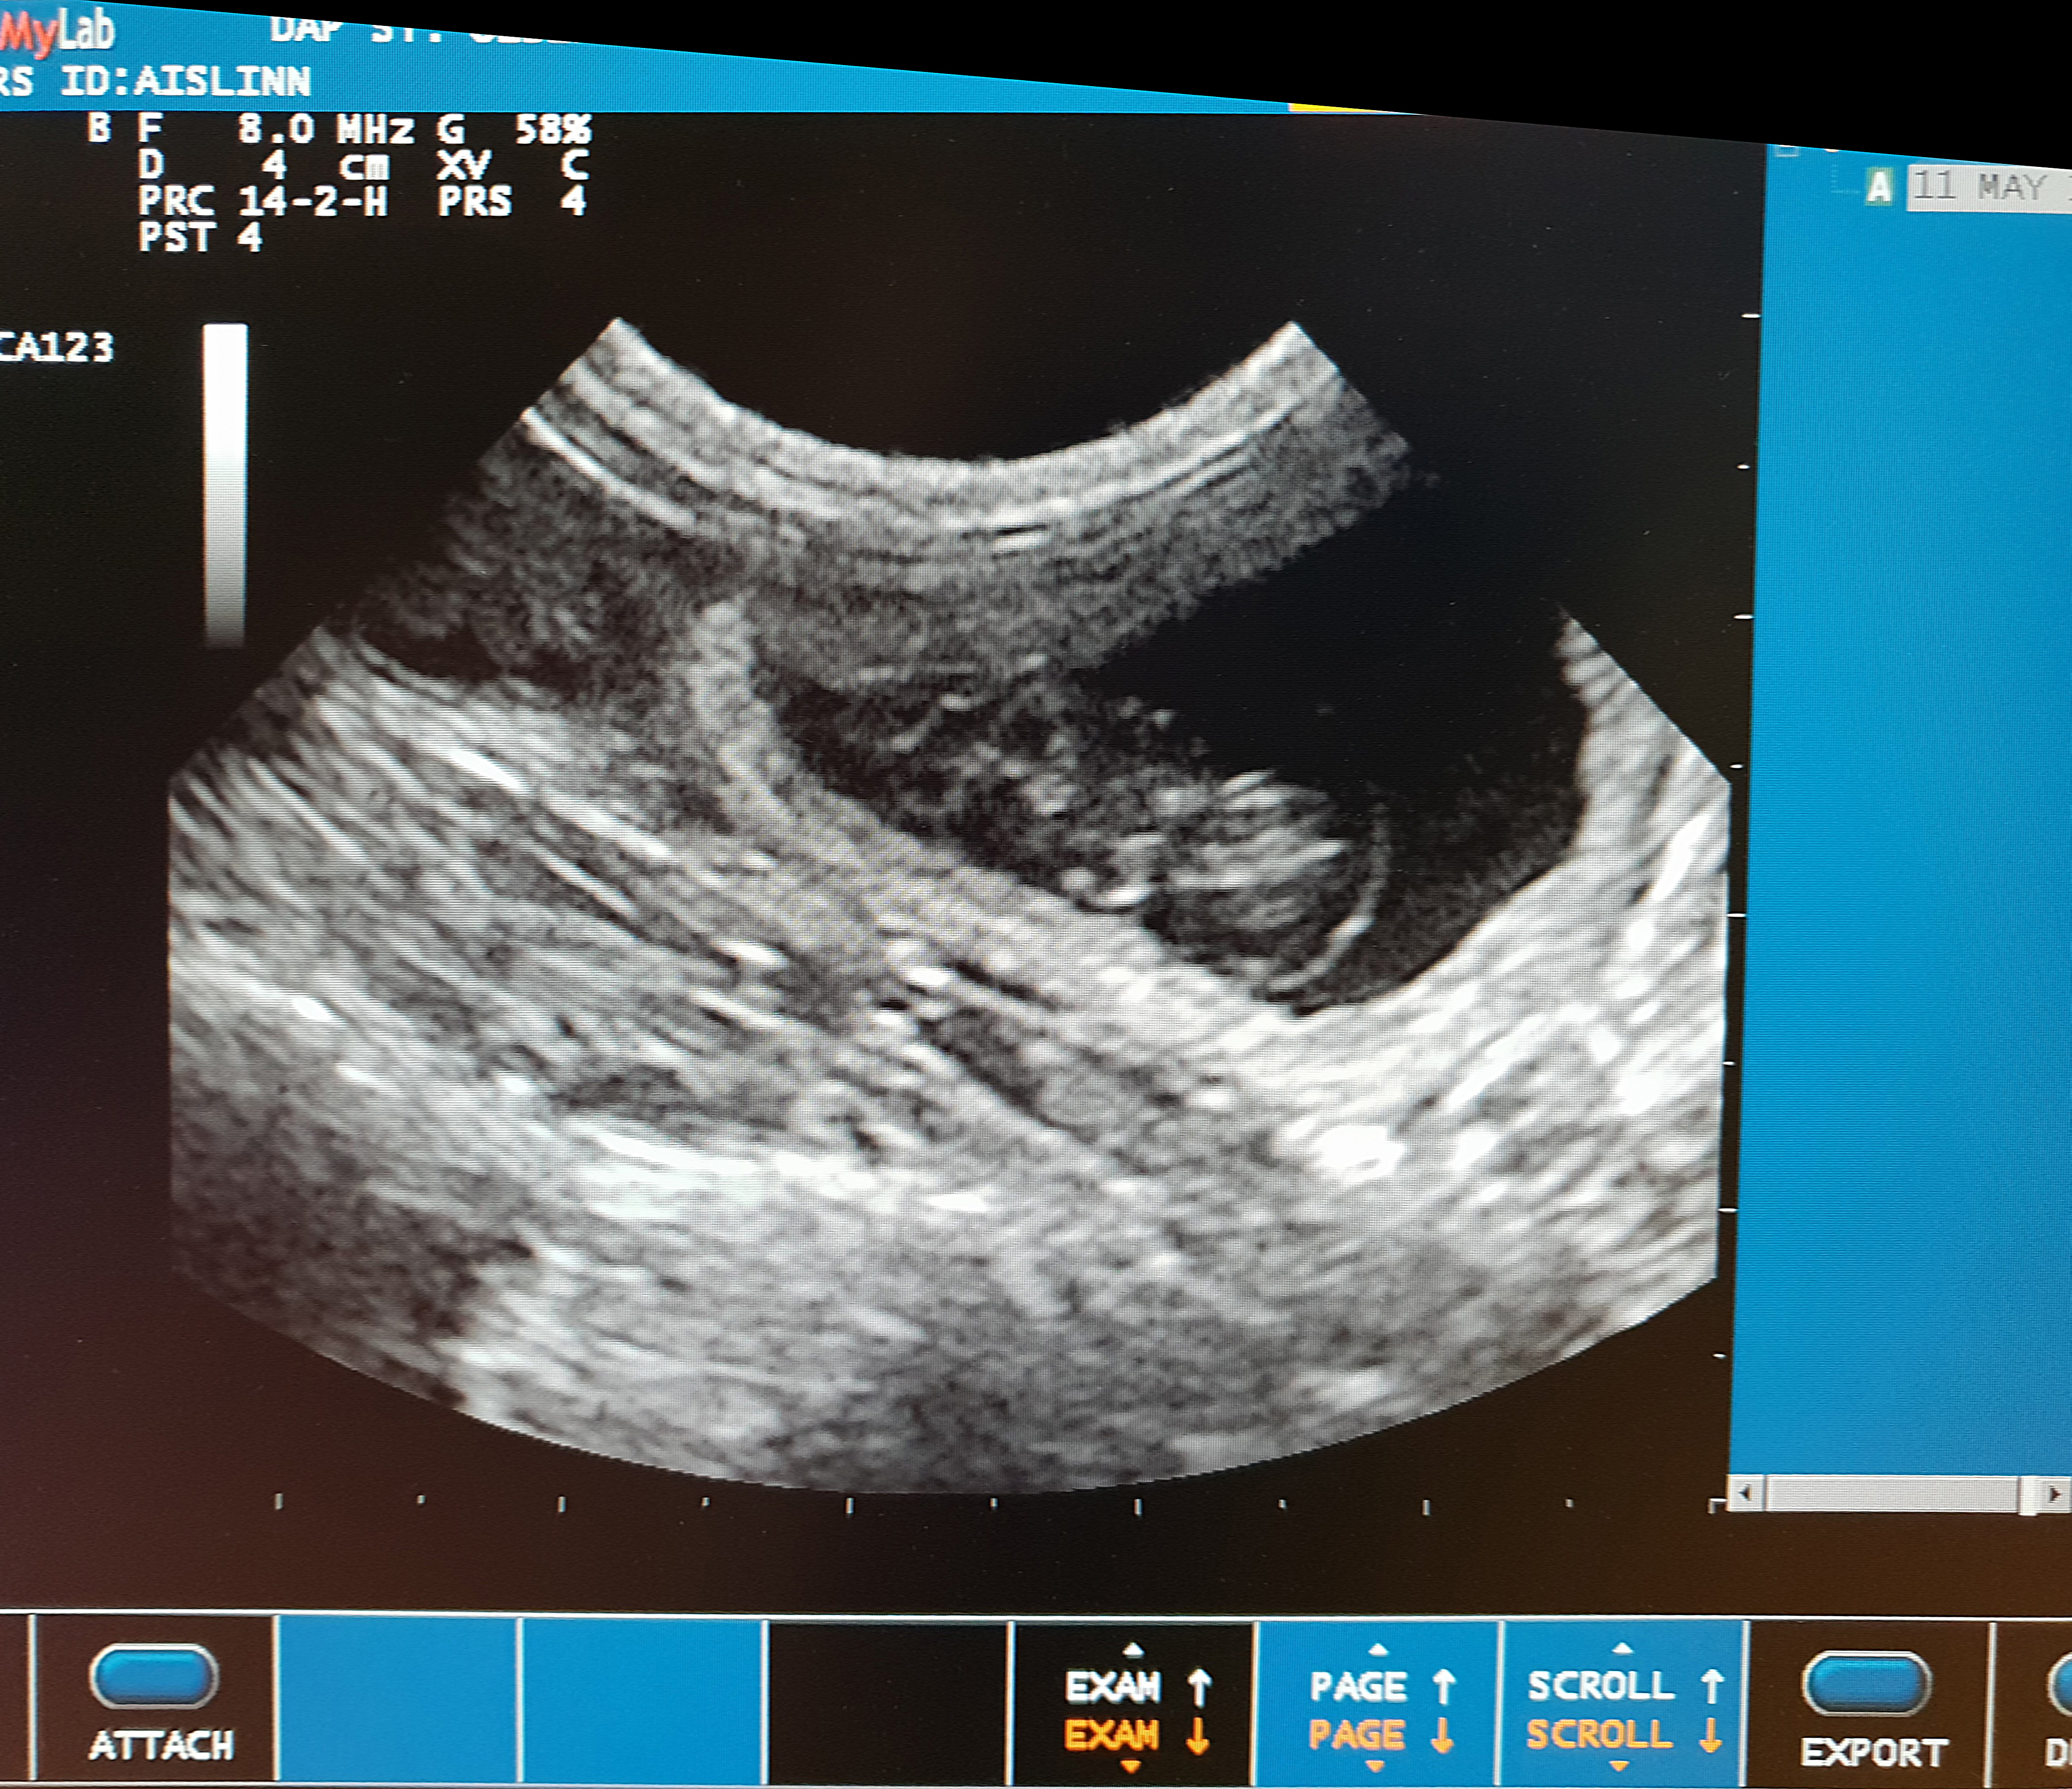

Voor zover we op de echo hebben gezien, groeien er minstens vier kittens in haar buikje.

De kittens worden in de tweede helft van juni verwacht.